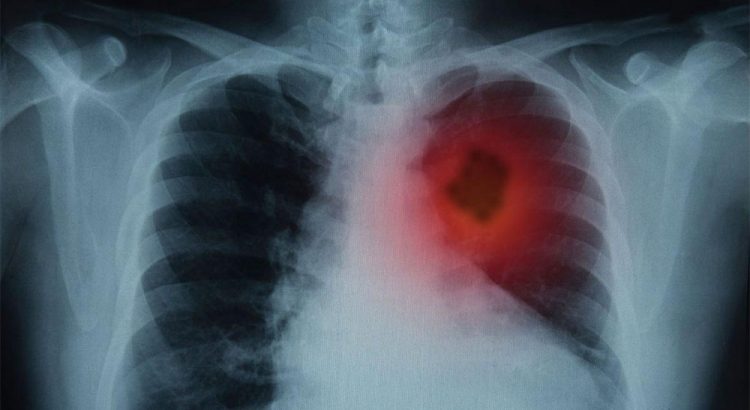

- Рентгенографія легень: первинний метод, що дозволяє побачити зміни в легеневій тканині.